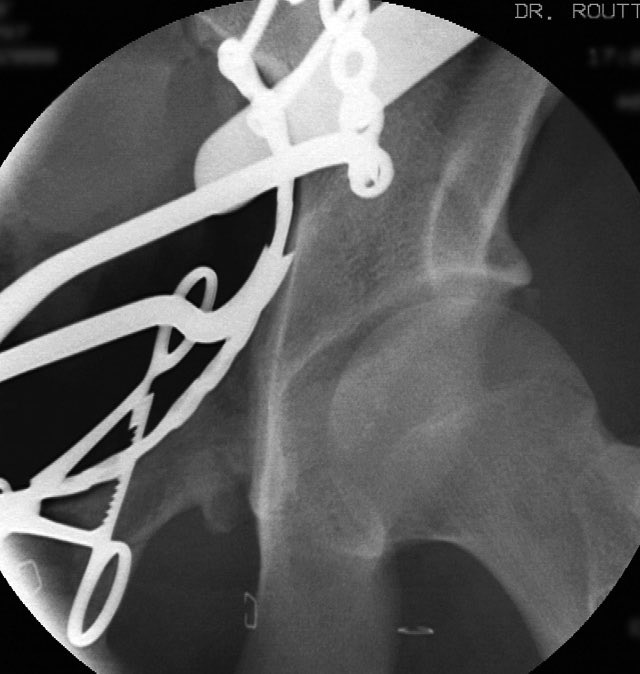

We used a regular table and an Ilioinguinal exposure to first reduce and stabilize the PC fragment to the intact ilium

Then reduced and clamped and stabilized the dome AC fragment

Then finished up the rest